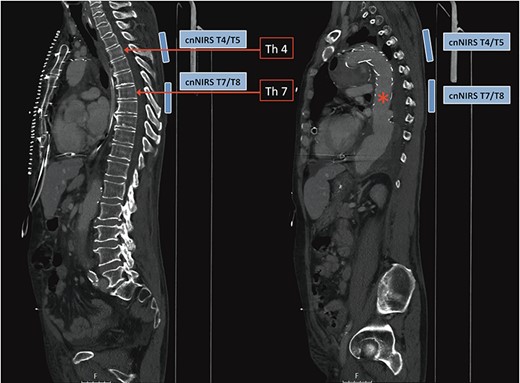

In recent and ongoing clinical and experimental research, our group developed a translational concept for non-invasive spinal cord monitoring during and after extensive aortic procedures using cnNIRS [4, 6]. Since experimental results on the optimal cnNIRS optode placement suggested that measurements are useful from the mid-thoracic region (from T7) [7], we used this novel placement pattern for the first time during surgery. Paravertebral optodes were placed bilaterally at the level of T4/T5 for reference and at the level T7/T8 for spinal cord oxygenation estimation during the procedure (Fig. 2). In this case, cerebrospinal fluid drainage was not utilized by default prior to the procedure.

Computed tomography image demonstrating collateral network near-infrared spectroscopy (cnNIRS) optode placement for the frozen elephant trunk procedure. Optodes were placed at the high thoracic level T4/5 as reference and at mid-thoracic level T7/8 for oxygenation measurements during the procedure. (Red asterisk) Marking the distal part of the stented prosthesis.